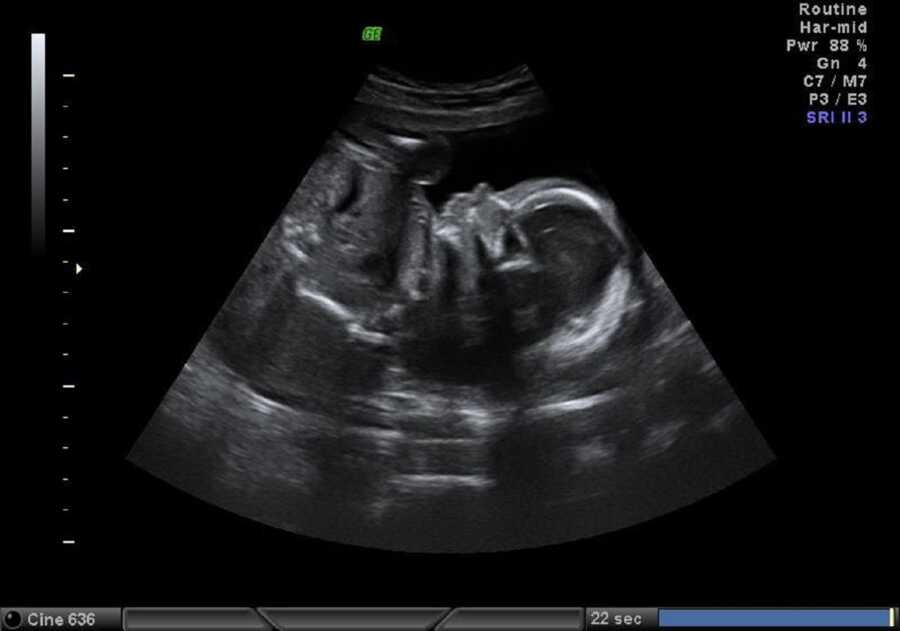

Her doctor did not treat her kindly. He dismissed her concerns, ignored Jordan, and set a due date that never seemed to fit. She knew he was breech when she felt the baby’s head high in her belly. The office insisted she couldn’t say, but an ultrasound proved her right. A C-section was booked for November 9 at eight in the morning. It wasn’t the birth she had imagined but the one ahead of her. On surgery day, the operating room felt cold and bright.